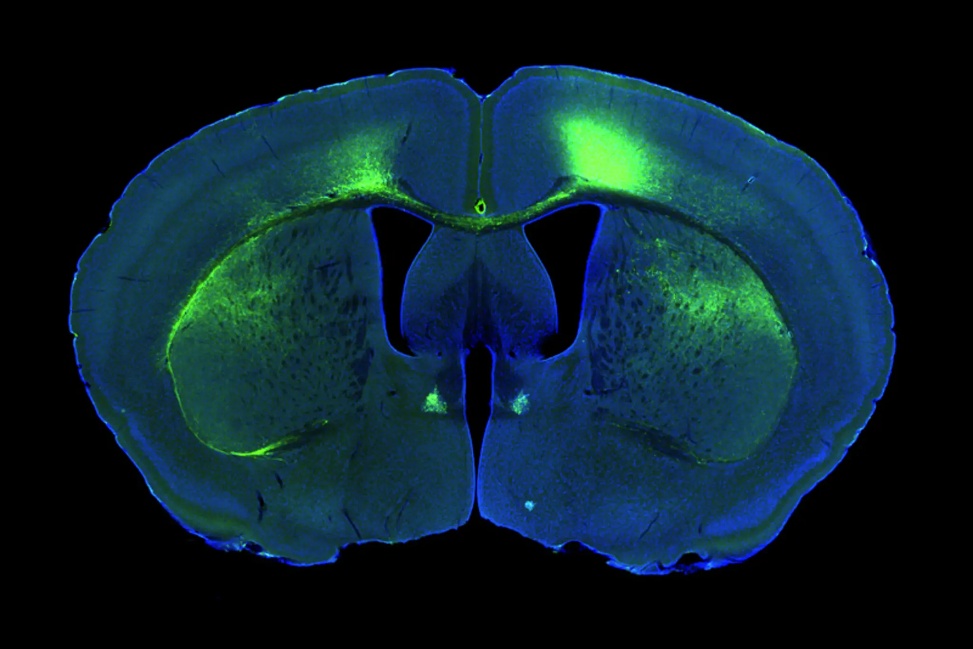

小鼠大脑的荧光显微照片